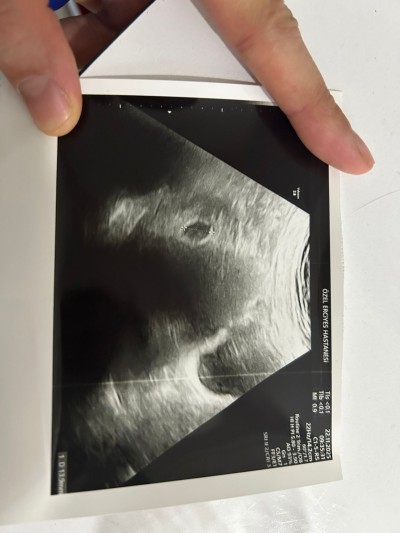

6+3 DE GİTTİĞİMDE GÖRÜNTÜ BU ŞEKİLDE. KALP ATIŞI VE BEBİŞ GÖZÜKMEDİ HENÜZ. GELECEK HAFTA TEKRAR GİDECEĞİM. 1.SORUM NORMAL Mİ? 2.SORUM DA ZOOM YAPIP BAKINCA UZUNLUK ÖLÇÜSÜNÜN SAĞ TARAFINDA YOLK SAC MI VAR YOKSA SÜREKLİ BAKMAKTAN BEYNİM BANA OYUN MU OYNUYOR??

Gebelik haftası 6

Merhaba dun bende gittim 6+3 doktor bakti kese gozukuyor 14 mml dedi ama bebek yok 10 gun sonra gel dedi yine bakariz bende 9 gun sonraya randevu aldim ilk cocuktadada bende hatirladigim kadariyla yine keseydi bebek gozukmemisti ama dun cox stres oldum

Benimki de tam öyle 14 mm çıktı baktıkça bir şeyler görüyorum